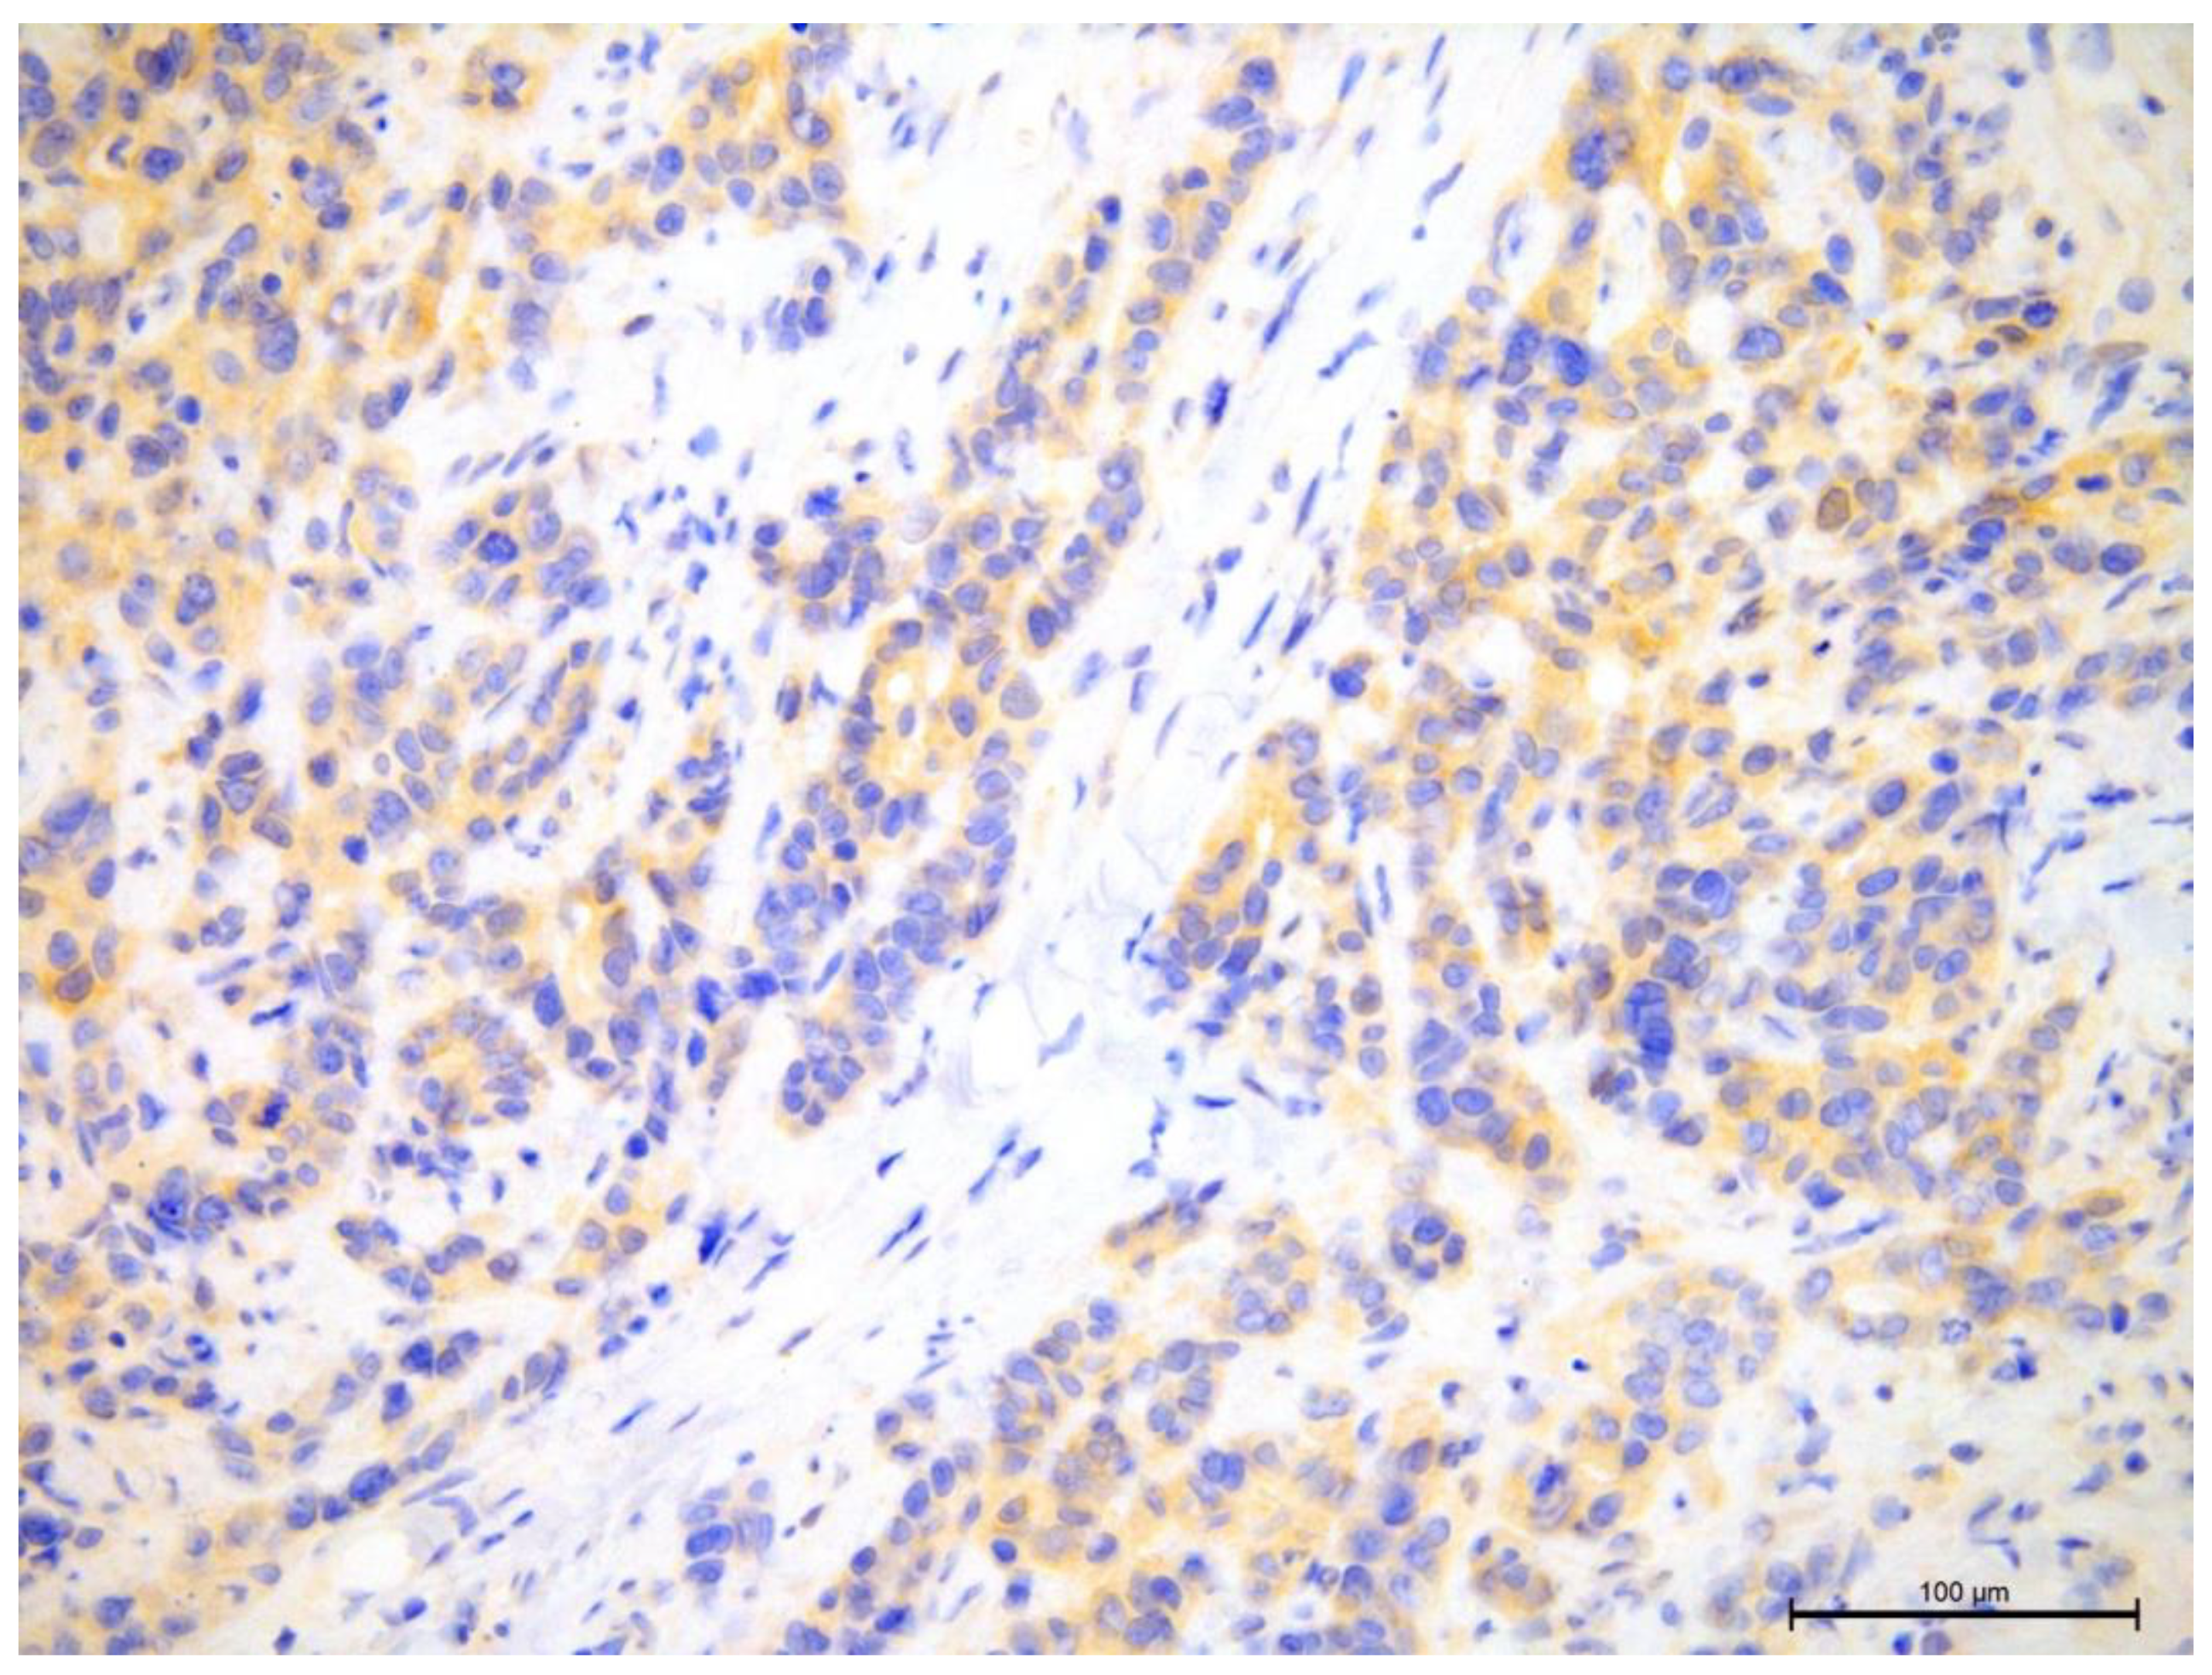

The androgen receptor expression was assessed in the tumor cell nuclei (Figure 13 and Figure 14).

Figure 13. Invasive breast cancer showing the lack of AR nuclear expression using anti-AR in the area of 200×.

Preprints 109573 g013

Figure 14. Invasive breast cancer showing 90% nuclear expression of the AR receptor using anti-AR in the area of 200×.

Preprints 109573 g014